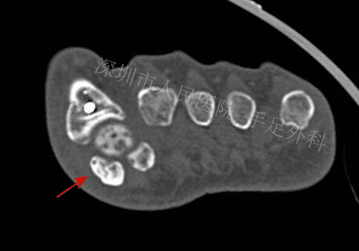

图11:患者拇外翻畸形,籽骨部位行走时疼痛。CT检查显示内侧籽骨较外侧明显增大(箭头),考虑为拇外翻合并籽骨炎。I期行拇外翻矫形+籽骨清理术,术后疼痛缓解,6个月后再次出现行走疼痛

图12:CT检查显示内侧籽骨增生,关节面不平整(箭头)